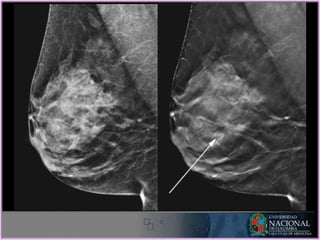

MLO

CC

Birads 4 - Sospechoso de

malignidad

Nódulo palpable